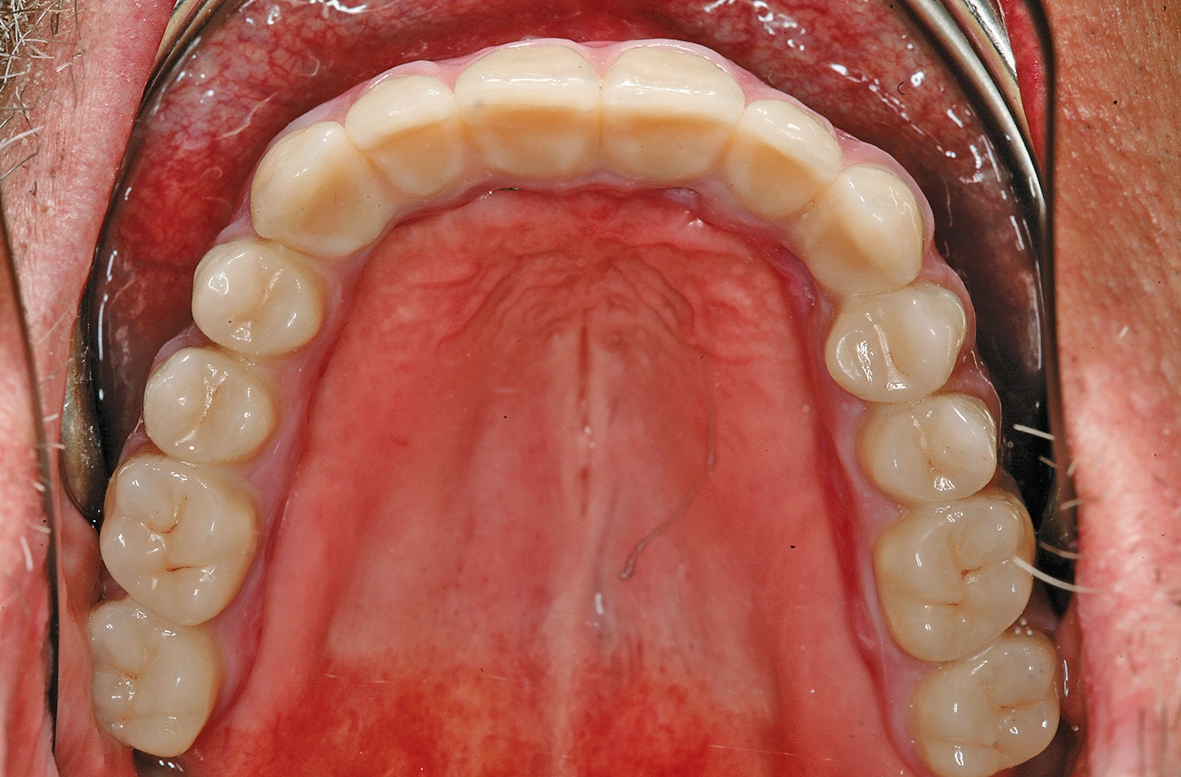

Eingliederung

Das Aufschrauben der definitiven Brücke gestaltete sich problemlos. Nach Abnahme der temporären Versorgung ist die fertiggestellte Brücke über die Prothetikkappen bzw. die Verbolzungen auf den Implantaten befestigt worden (Abb. 5 und 6). Bei den posterioren Implantaten wurde der Schraubenzugang vom Zahntechniker nach vestibulär – außerhalb des sichtbaren Bereichs – gelegt (Abb. 7 und 8). Die anderen Implantate wurden im palatinalen Bereich verschraubt (Abb. 9). Aufgrund der Drei-Punkt-Fixierung ist ein Verkippen oder das Rotieren des Zahnersatzes ausgeschlossen. Da die Schraube in der Sekundärkonstruktion „gefangen“ ist, wird die Anwendung im Mund erleichtert. Ein lästiges Einfädeln entfällt. Bereits mit zwei bis drei Umdrehungen ist eine Schraube fixiert. Weder ästhetisch noch funktionell treten Beeinträchtigungen auf.

Abschließend wurden die funktionellen, ästhetischen und parodontal- hygienischen Faktoren überprüft und dem Patienten entsprechende Hinweise zur adäquaten Reinigung des Zahnersatzes gegeben (Abb. 10 und 11). Bei einem regelmäßigen Recall (idealerweise aller drei Monate) kann die Brücke aufgrund der transversalen Verschraubung sehr einfach gelöst und alle erforderlichen Mundhygienemaßnahmen vorgenommen werden.